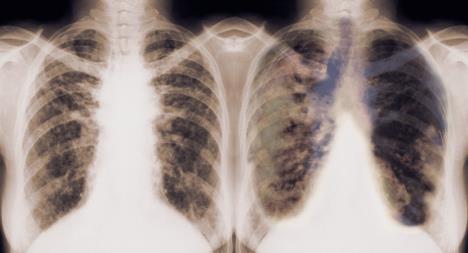

- Rana dijagnostika je zaista teško ostvariva, ali je ideal kome se teži. Metode su usmerene na otkrivanje i procenu lokalizacije, veličine, vrste i odnosa patoloških procesa. Dijagnostički tim predstavljaju hirurg, radiolog i patolog. Sarađujemo i sa lekarima drugih specijalnosti. Počinje se sa standardnom radiografijom, laboratorijom, spirometrijom, skenerom, magnetnom rezonancom, citološkim pregledom sputuma, bronhoskopijom, biopsijom...

- Predisponirajući faktori za nastanak karcinoma pluća su, uz česte infekcije disajnih organa koje se ponavljaju sa iste strane pluća, prethodna bronhopulmonalna oboljenja. Među njima se uglavnom pominju fibrozni alveolitis, tuberkuloza, sarkoidoza, kongenitalna cistična bolest pluća.

Često neprimetno napreduje, a kada se pojave specifični problemi - rak pluća je već uznapredovao. Na oboljenje ukazuju neobjašnjivi umor, otežano disanje (nedostatak vazduha), bol u grudnom košu, kašalj (suv ili sa sekretom), iskašljavanje sukrvice ili krvi, gubitak apetita i telesne težine, bol u ramenu, otok vrata i lica.